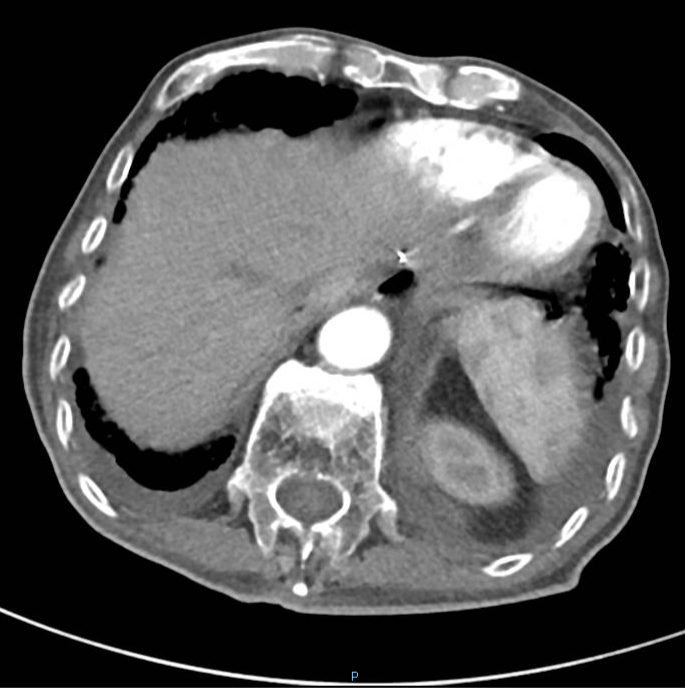

强化CT:1、符合胃部分切除术后,吻合口壁增厚伴食管下段扩张;2、胆囊结石:胆总管结合;3、肠淤张;4、前列腺增大;5、动脉硬化。

PET-CT检查:1、胃癌大部切除术后改变;肝左外叶近包膜下高代谢结节(于临近胃食管吻合口分界欠清),考虑肝转移。2、右肺中上叶多发结节伴代谢轻度增高;双肺间质纤维化;双肺泡性气肿;经根部气管憩室;贫血;动脉硬化;双侧胸膜增厚;右肺门及纵隔内多发淋巴结增生。

行CT引导下肺部肿物穿刺活检术,病理回报:(肺穿刺物)结合HE形态及IHC支持为腺癌,结合病史及IHC表型考虑转移可能性大,请结合临床。免疫组化结果:TTF-1(-),HER2(+++)

△ 2019.7影像学检查